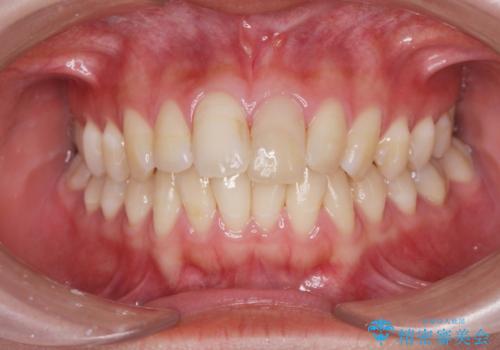

前歯の変色を改善するセラミッククラウン治療

- 以前に前歯を強打し、変色してきた前歯の審美性の改善を希望されて来院されました。

X線検査の結果、変色をきたしている歯は根尖病変が存在し、神経が失活している状態でした。

根管治療を行ったのち、セラミッククラウンで審美性を改善していきます。

歯科技工士との綿密な打ち合わせで、非常に自然なセラミッククラウンを作製することができました。